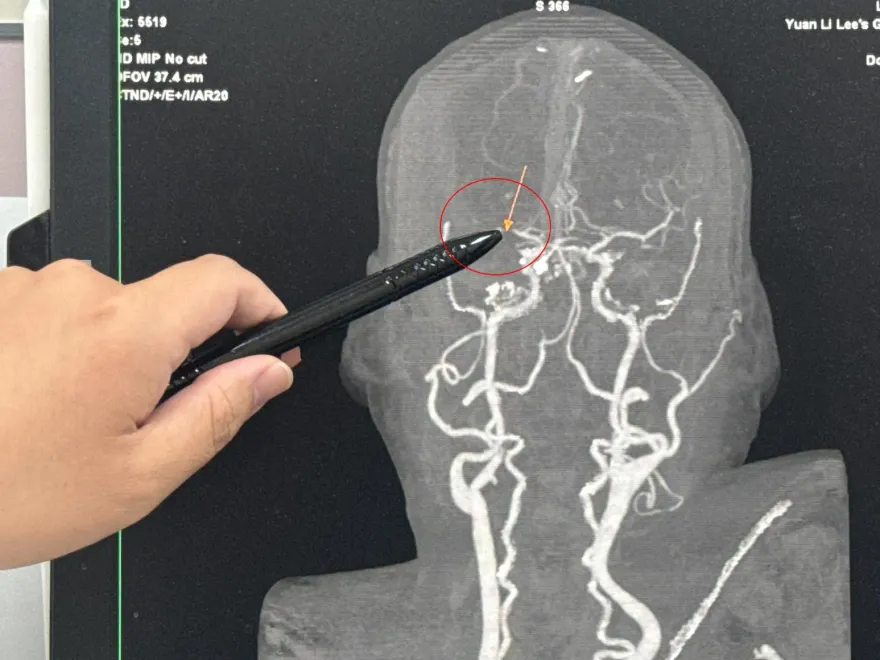

腦動脈瘤

腦溢血

健檢

百萬YouTuber

腦部MRI